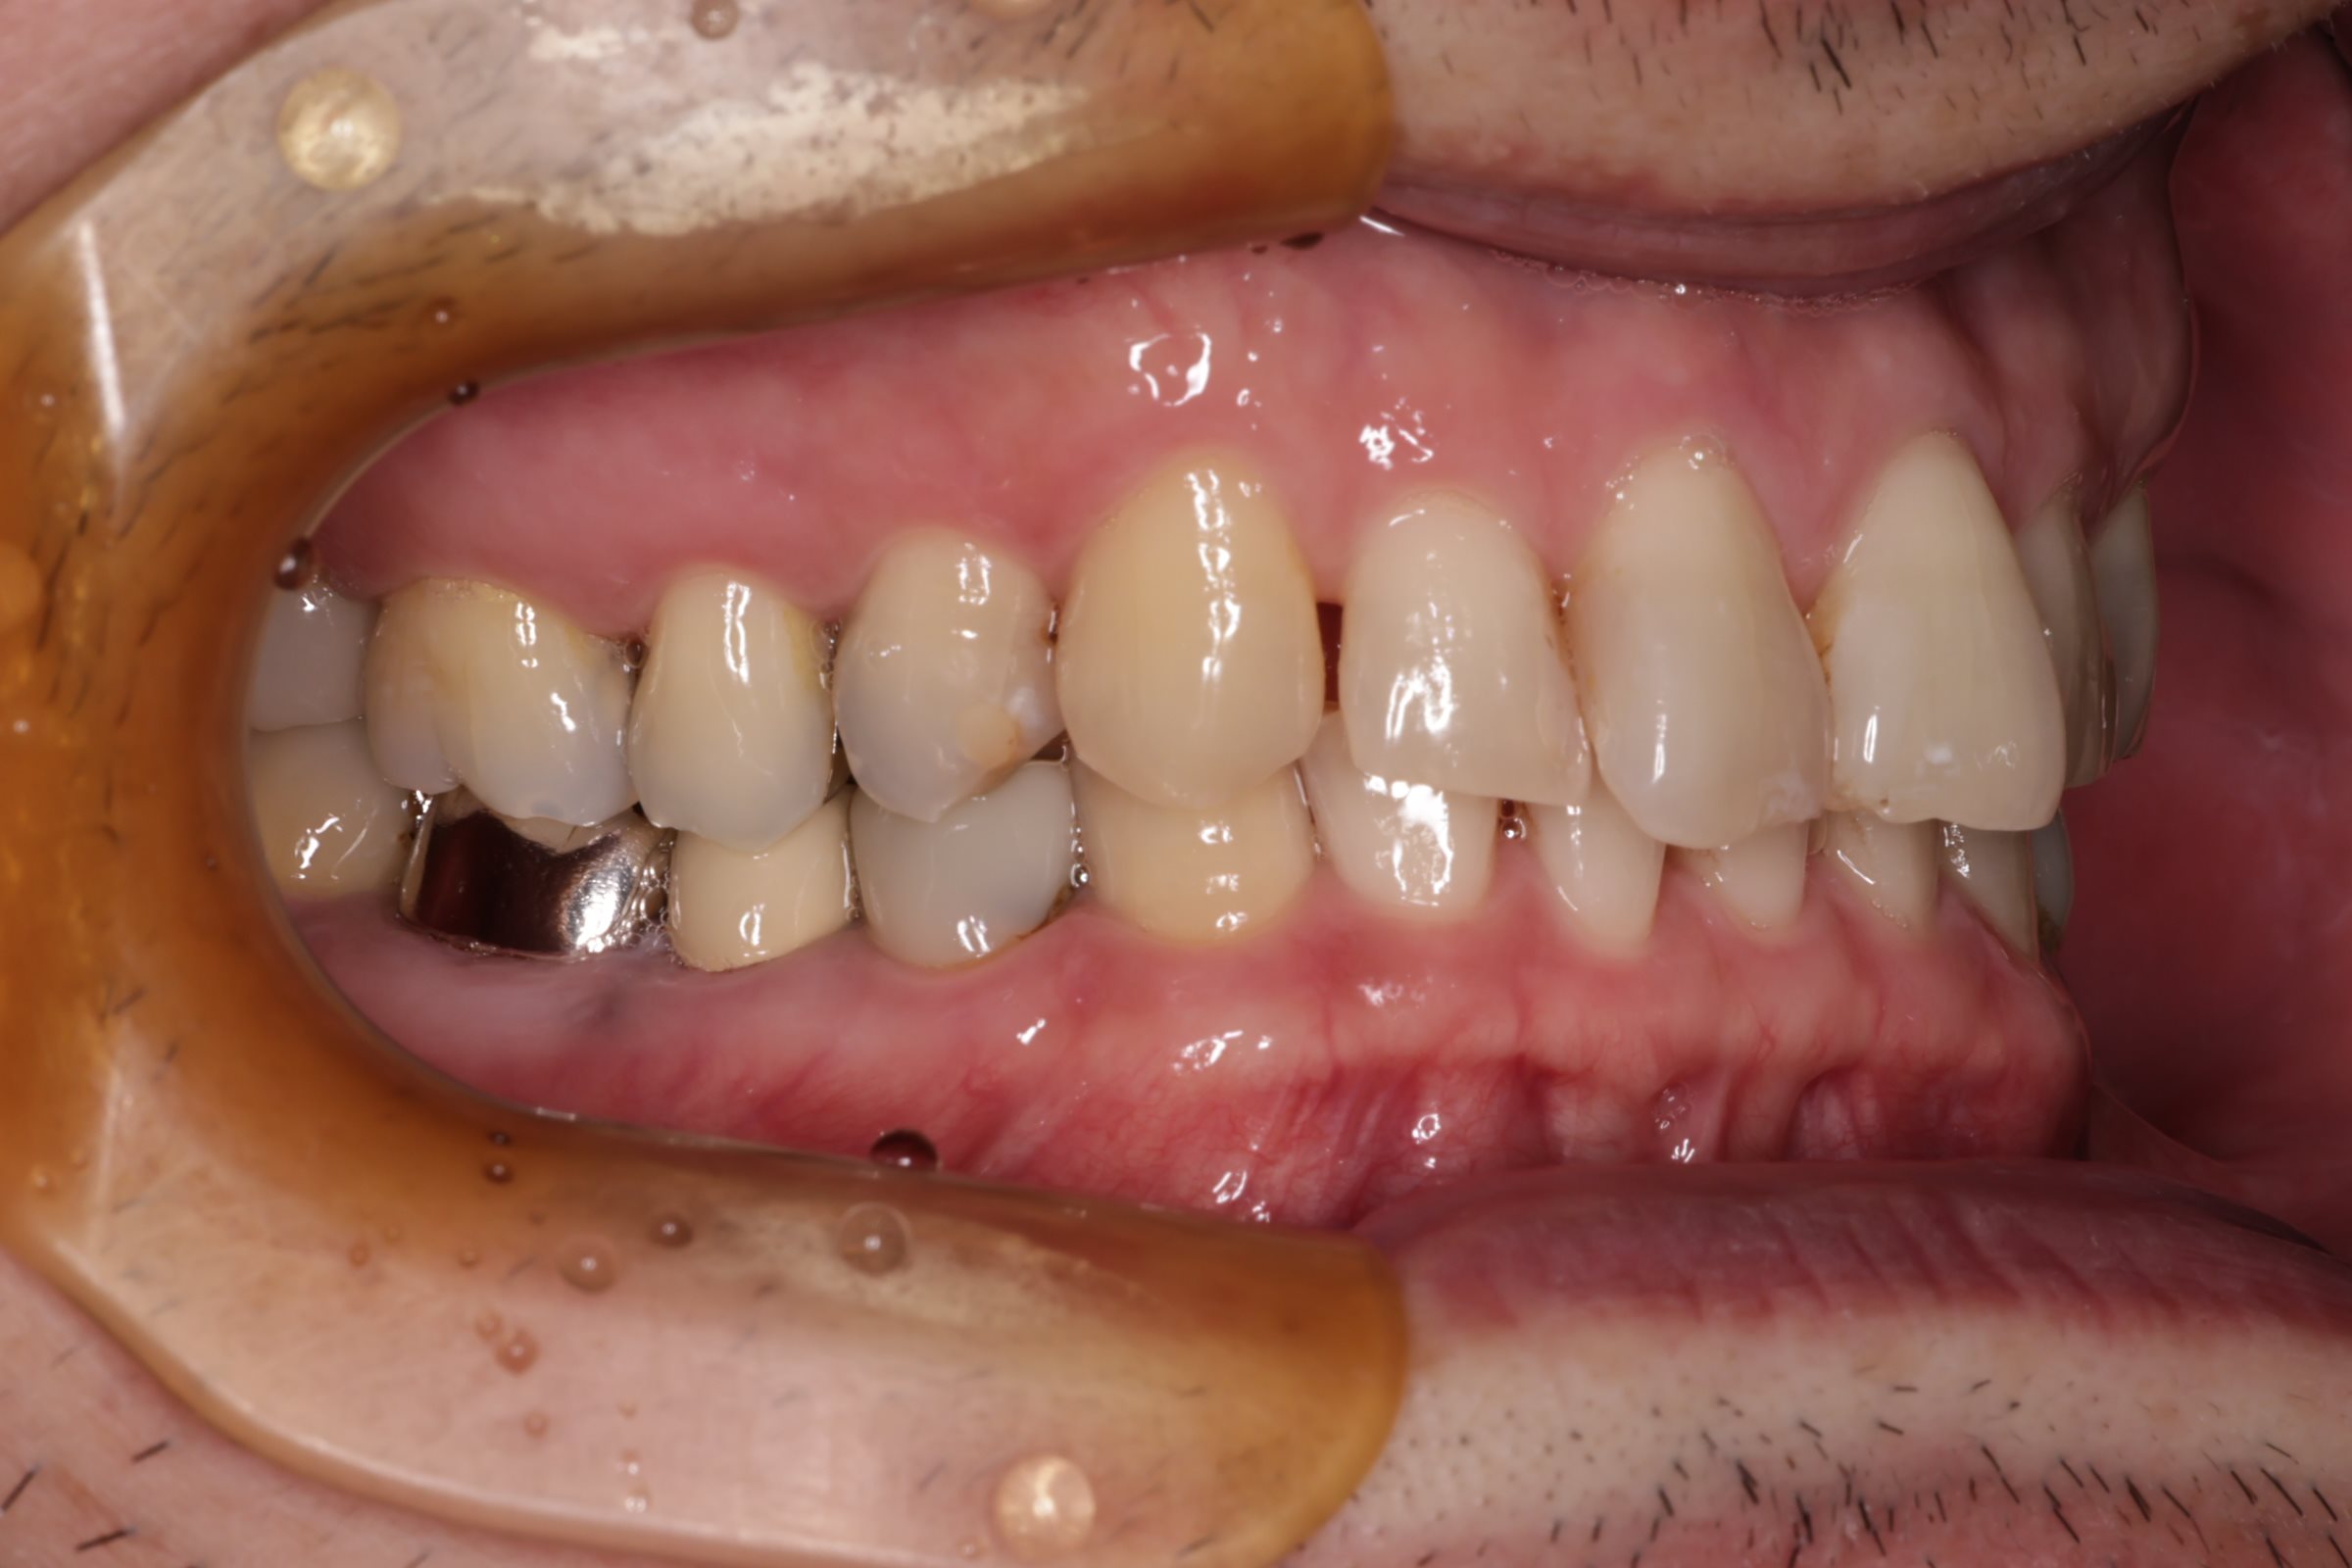

初診時の口腔内の状態:

口腔内には多数の銀歯(銀合金)が確認されました。患者様は過去に多くの虫歯治療を受けており、そのほとんどが保険適用内の銀合金で修復されていました。

患者様はパッチテストによりニッケルなどに対するアレルギーを持っていることが確認されており、口腔内の銀合金もアレルギーの原因となっている可能性が高いと診断しました。また、レントゲン画像を確認すると、被せ物や詰め物の内部、あるいは隙間から、虫歯(カリエス)や根の細菌感染が疑われる状態も確認されました。

Before